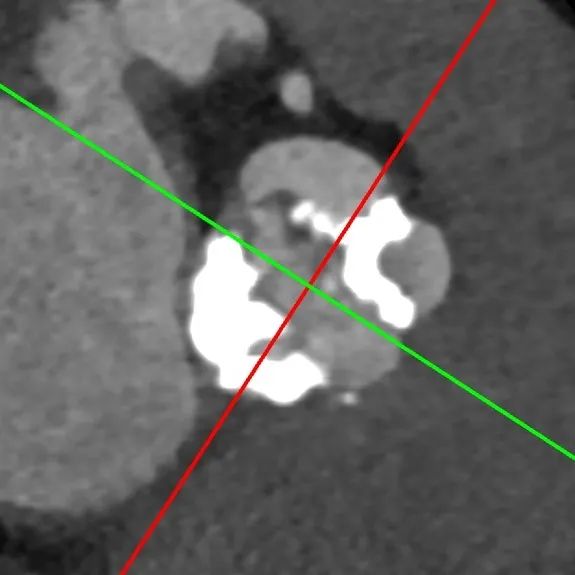

主动脉CT

瓣环85.7mm,平均径26.7mm,LOT周长88.5mm,平均径27.5mm,瓣叶L-R融合,瓣叶重度钙化,钙化主要分布于右瓣叶、无冠瓣和左右瓣叶融合脊,瓣上4/6mm,预计推开空间周长84.5mm。

冠脉风险高:左冠高度6.8mm,瓣叶10mm,左冠高风险,右冠风险可控。

升主动脉瘤样扩张,平均径57mm,且横位心71°,存在升主动脉破裂风险。

第二例病人同样为高难度病例,Type1型L-R融合二叶瓣,钙化积分1300,瓣叶增厚、轻度钙化,钙化分布于瓣叶及左右瓣叶融合脊。

瓣环周长87.4mm,平均径27.1mm。LVOT周长90.5mm,平均径28.5mm。

瓣上4mm/6mm,预估可推开空间周长81.8mm/75.8mm。